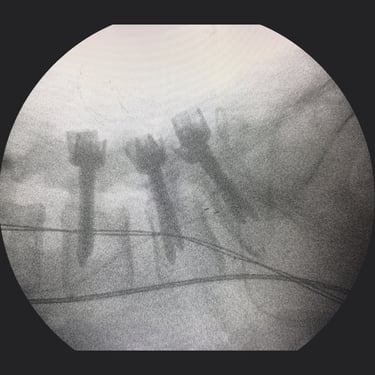

Columna lumbar inestable con listesis: tratamiento con artrodesis y tornillos transpediculares

La listesis lumbar ocurre cuando una vértebra se desplaza hacia adelante o hacia atrás respecto a la vértebra inferior, generando inestabilidad de la columna lumbar. Esta condición puede causar dolor lumbar crónico, compresión nerviosa, ciática, debilidad en las piernas o dificultad para caminar. Cuando el tratamiento conservador no es suficiente, la artrodesis lumbar con tornillos transpediculares es una alternativa quirúrgica eficaz. Este procedimiento permite fijar las vértebras afectadas mediante implantes que estabilizan la columna y favorecen la fusión ósea. Con técnicas modernas y abordajes mínimamente invasivos, se logra aliviar el dolor, mejorar la estabilidad vertebral y recuperar la función del paciente.